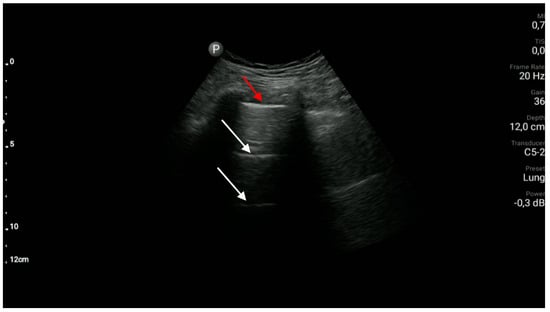

- The sonographic features of interstitial lung disease involving pulmonary fibrosis are as follows: the lung sliding sign, the presence of ≥3 B-line artifacts in one intercostal space (a longitudinal scan plane in relation to the body axis) and pleural line abnormalities. (A1)

- Pleural line abnormalities found in patients with pulmonary fibrosis are described as irregular, coarse in appearance, fragmented or blurred.

- The sonographic features of interstitial syndrome are as follows: the presence of lung sliding and ≥3 B-line artifacts in one intercostal space in a single longitudinal scan plane (in relation to the body axis). (A1)

- B-line artifacts are laser-like vertical reverberation artifacts arising from the pleural line, extending to the bottom of the screen, and moving along with the movements of the pleural line. The definition of a B-line artifact is based on the use of convex/micro-convex transducers.